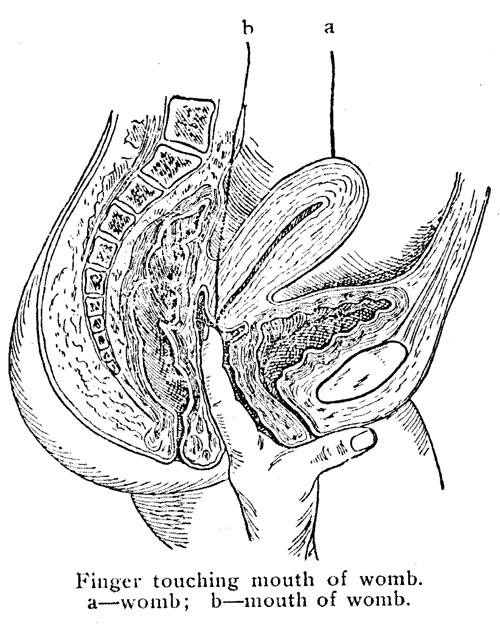

Follow the directions given with each box, and learn to adjust it correctly; one can soon feel that it is on right. After the pessary has been placed into the vagina deeply, it can be fitted well over the neck of the womb. One can feel it is fitted by pressing the finger around the soft part of the pessary, which should completely cover the mouth of the womb. If it is properly adjusted there will be no discomfort, the man will be unconscious that anything is used, and no germ or semen can enter the womb.

Finger touching mouth of womb.

a—womb; b—mouth of womb.

Finger touching mouth of womb.

a—womb; b—mouth of womb.